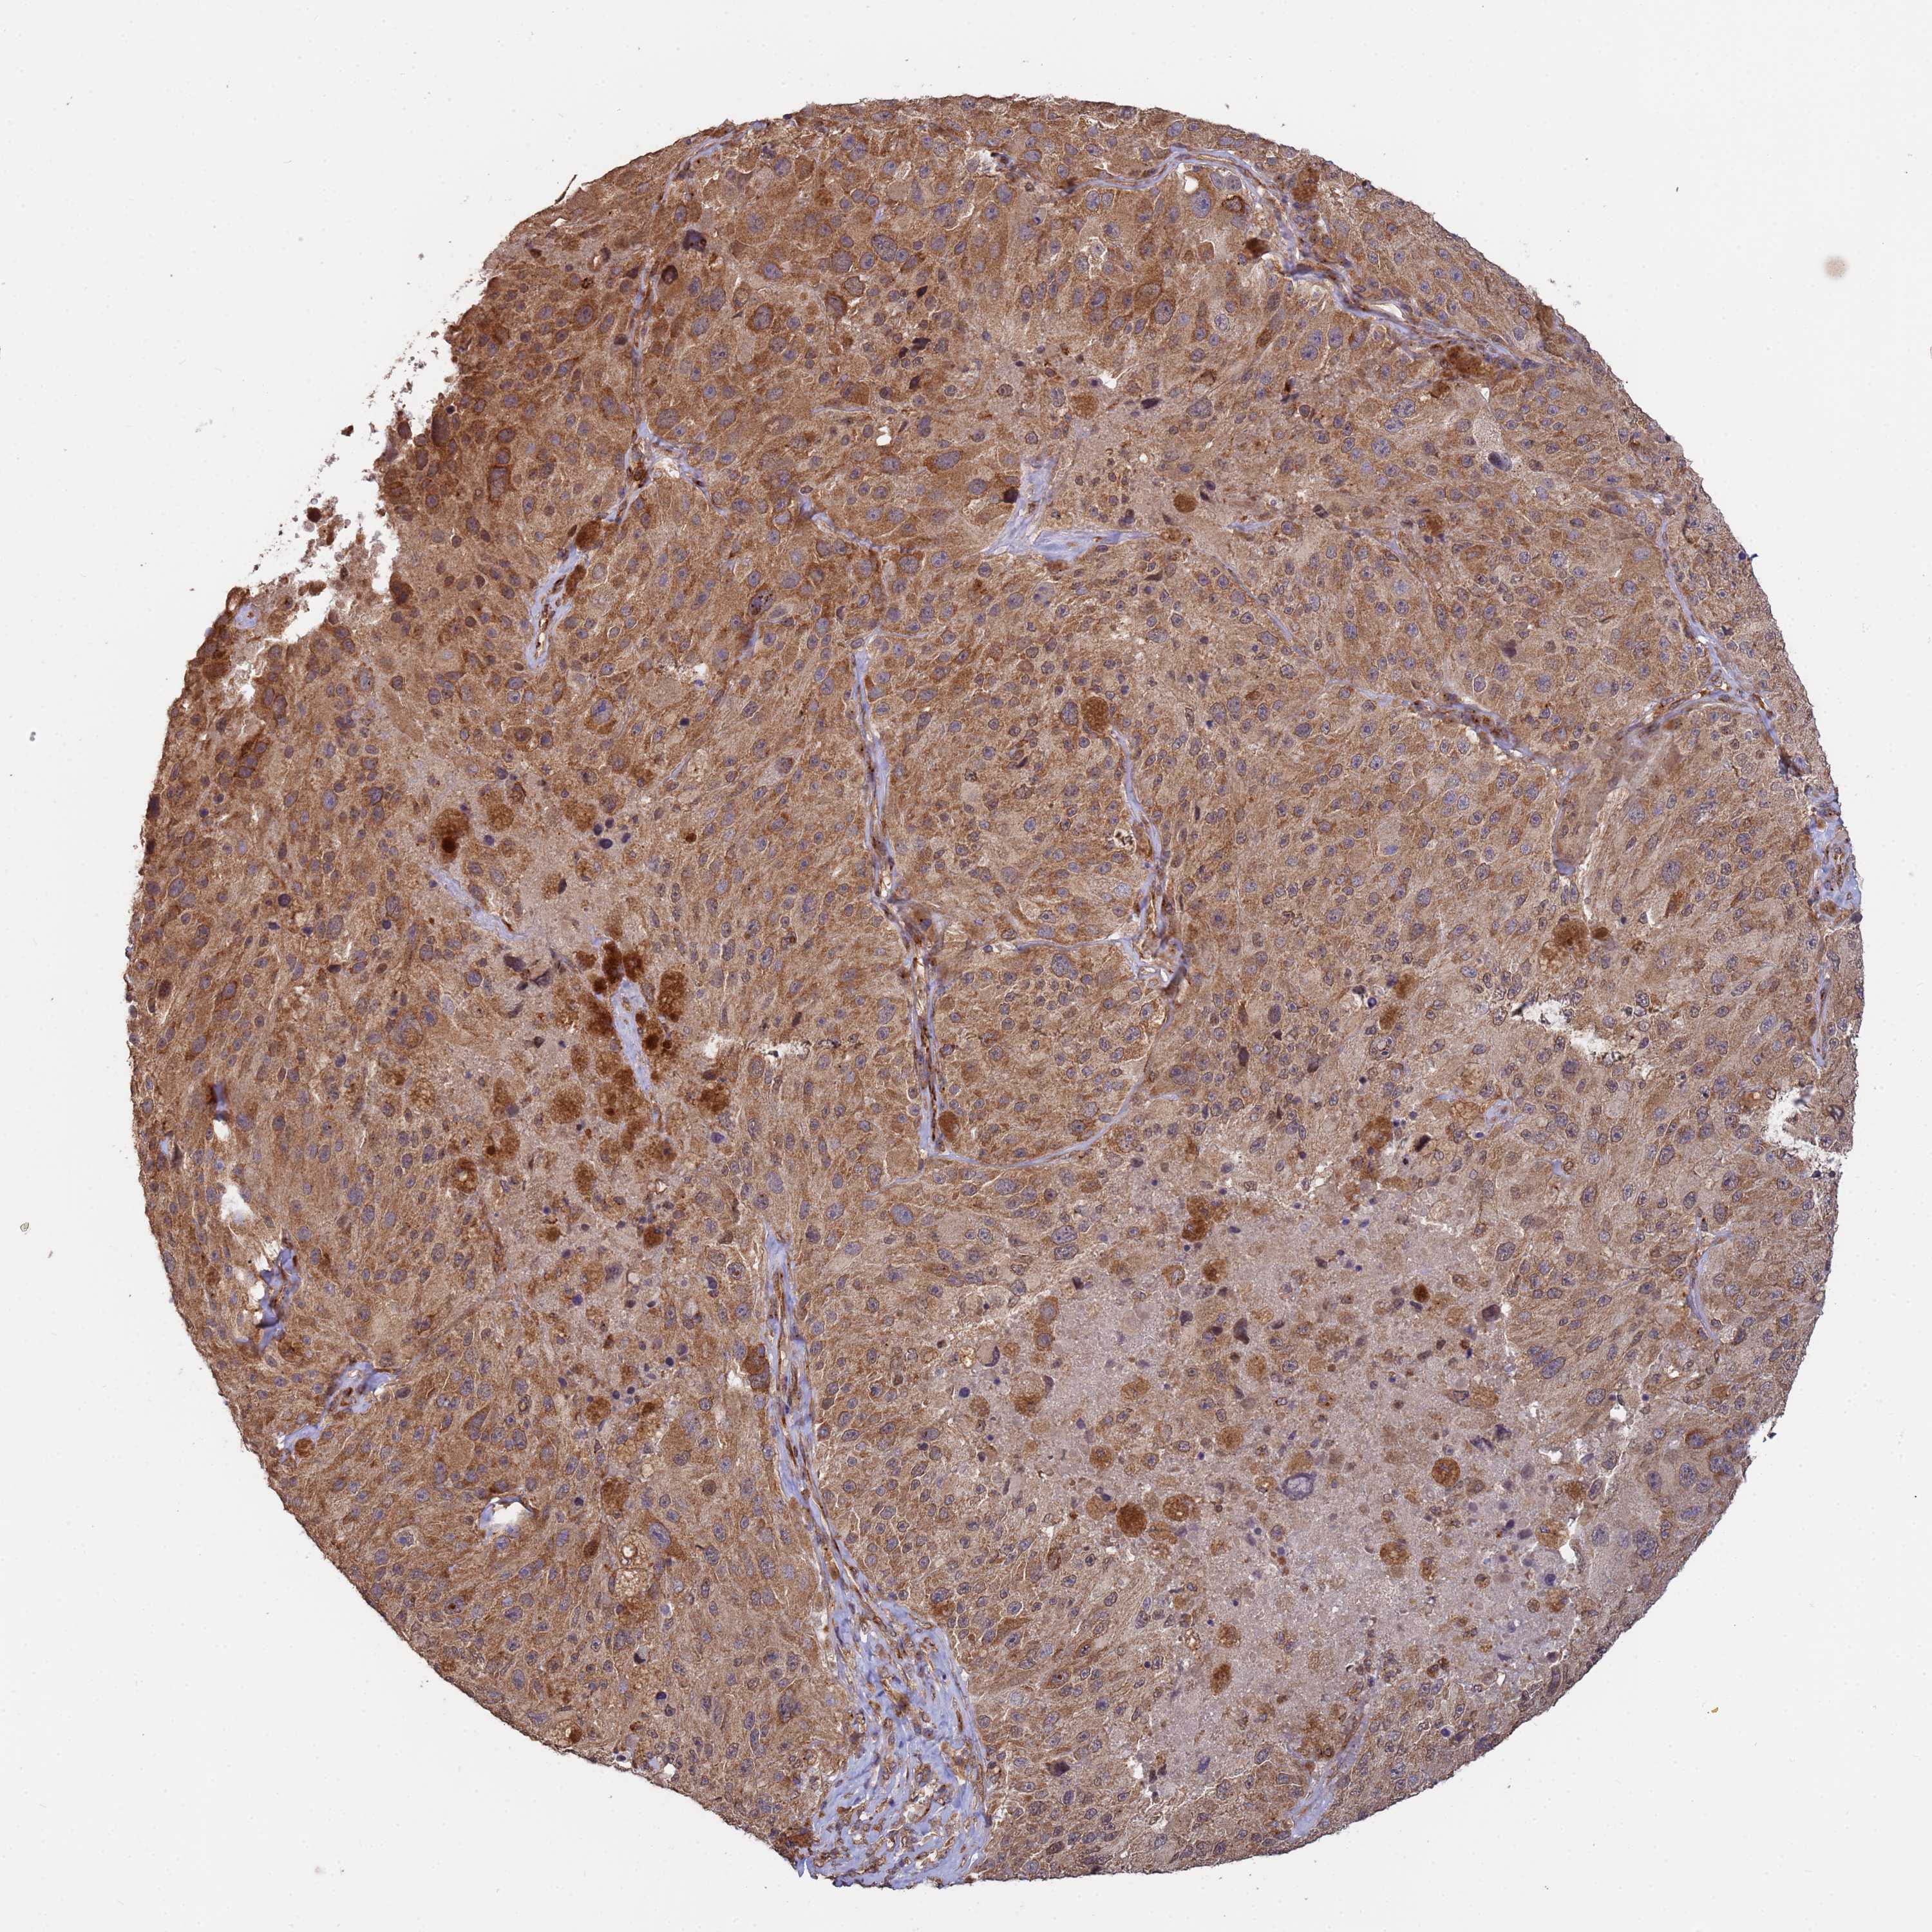

MELANOMA - Protein expressioni

A mouse-over function shows sample information and annotation data. Click on an image to view it in a full screen mode. Samples can be filtered based on level of antibody staining by selecting one or several of the following categories: high, medium, low and not detected. The assay and annotation is described here.

Note that samples used for immunohistochemistry by the Human Protein Atlas do not correspond to samples in the TCGA dataset.

Antibody stainingi

Antibody staining in the annotated cell types in the current human tissue is reported as not detected, low, medium, or high, based on conventional immunohistochemistry profiling in selected tissues. This score is based on the combination of the staining intensity and fraction of stained cells.

Each image is clickable and will lead to virtual microscopy that enables deeper exploration of all samples and also displays staining intensity scores, fraction scores and subcellular localization as well as patient and tissue information for each sample.

Antibody HPA045624

Staining

High

Medium

Low

Not detected

Intensity

Strong

Moderate

Weak

Negative

Quantity

>75%

75%-25%

<25%

None

Location

Nuclear

Cytoplasmic/membranous

Cytoplasmic/membranous,nuclear

Malignant melanoma, NOS

Malignant melanoma, Metastatic site